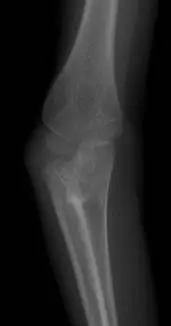

本題提供兩張前臂/肘關節 X 光影像(前後位及側位):

圖一(前後位 AP view):可見肘關節及近端橈尺骨區域。橈骨頭(radial head)與近端尺骨呈現異常接近,近端橈尺骨交界處有骨性連結跡象,正常的橈尺近側關節(proximal radioulnar joint)間隙消失,提示兩骨近端發生融合(synostosis)。

這兩張影像與先天橈尺骨黏合的典型 X 光表現相符:近端橈尺骨骨性融合,橈骨頭形態改變(可伴隨橈骨頭後脫臼),前臂固定於旋前(pronation)位置。